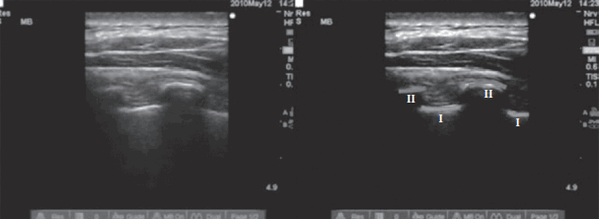

На рисунках 2—4 представлены иллюстрации УЗИ паравертебрального пространства. Слева показаны анатомические ориентиры — париетальная плевра, поперечный отросток до введения МА, после введения МА и постановки катетера. На иллюстрациях справа линиями обозначены те же анатомические ориентиры [15].

Рис. 2. Определение паравертебрального пространства УЗ-навигацией

(линии I — париетальная плевра, линии II — очертание поперечного отростка

(Medical Ultrasonography 2010; 12 (3): 223—227)